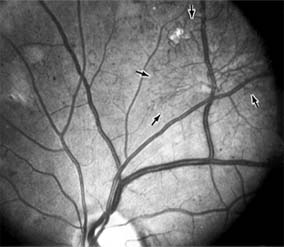

Chapter 10: Retina RETINAL VASCULAR DISEASES DIABETIC RETINOPATHY Diabetic retinopathy is one of the leading causes of blindness in the Western world. The view that chronic hyperglycemia of diabetes mellitus is the major determinant of diabetic retinopathy is supported by the observation that retinopathy in young people with type I (insulin-dependent) diabetes does not occur for at least 3-5 years after the onset of this systemic disease. Similar results have been obtained for type II (non-insulin-dependent) diabetes, but in such patients the time of onset and therefore the duration of disease are more difficult to determine precisely. It is recommended that patients with type I diabetes mellitus be referred for ophthalmologic examination within 3 years after diagnosis and reexamined on at least an annual basis. Type II diabetic patients should be referred for ophthalmologic examination at the time of diagnosis and reexamined at least annually. As diabetic retinopathy can become particularly aggressive during pregnancy, any diabetic woman who becomes pregnant should be examined by an ophthalmologist in the first trimester and at least every 3 months thereafter until parturition. In terms of both prognosis and treatment, it is useful to divide diabetic retinopathy into nonproliferative and proliferative categories. The prevalence of proliferative retinopathy in type I diabetics with 15 years of systemic disease is 50%. While the prevalence of proliferative disease at 15 years is much less in type II diabetics, the prevalence of macular edema as a function of the duration of systemic disease is the same in both groups. 1. NONPROLIFERATIVE DIABETIC RETINOPATHY Diabetic retinopathy is a progressive microangiopathy characterized by small vessel damage and occlusion. The earliest pathologic changes are thickening of the capillary endothelial basement membrane and reduction of the number of pericytes. Background diabetic retinopathy is a clinical reflection of the hyperpermeability and incompetence of involved vessels. The capillaries develop tiny dot-like outpouchings called microaneurysms, while the retinal veins become dilated and tortuous (Figure 10-20). Multiple hemorrhages may appear throughout different levels of the retina. Flame-shaped hemorrhages are so shaped because of their location within the horizontally oriented nerve fiber layer, while dot and blot hemorrhages are in the deeper retina, where cells and axons are vertically oriented. Macular edema is the most frequent cause of visual loss among patients with background diabetic retinopathy. The edema is caused primarily by a breakdown of the inner blood-retinal barrier at the level of the retinal capillary endothelium, allowing leakage of fluid and plasma constituents into the surrounding retina. The edema may be focal or diffuse and appears clinically as thickened, cloudy retina with associated microaneurysms and intraretinal exudate. Circinate zones of yellow, lipid-rich exudate may form around clusters of microaneurysms and are most frequently centered in the temporal portion of the macula. While the prevalence of macular edema is 10% in the diabetic population as a whole, there is a dramatic increase in prevalence in eyes with more severe retinopathy. With progressive microvascular occlusion, signs of increasing ischemia may be superimposed on the picture of background retinopathy and produce the clinical picture of preproliferative diabetic retinopathy. The most typical findings here are multiple cotton-wool spots, beading of the retinal veins, and irregular segmental dilation of the retinal capillary bed (intraretinal microvascular abnormalities). Closure of retinal capillaries surrounding the foveal avascular zone may cause significant ischemia, manifest clinically by the presence of large dark retinal hemorrhages and small thread-like macular arterioles. Eyes with macular edema and significant ischemia have a poorer visual prognosis-with or without laser treatment-than eyes with edema and relatively good perfusion. The visual and electrophysiologic dysfunctions associated with diabetes probably result from the local vascular abnormalities and the systemic metabolic effects of the disease to which the retina is subjected. A characteristic blue-yellow color vision abnormality develops, and hue discrimination may be impaired. Contrast sensitivity may be reduced in patients, even in the presence of normal visual acuity. Visual field testing may show relative scotomas corresponding to areas of retinal edema and nonperfusion, and abnormalities in dark adaptation have also been described. Electroretinographic abnormalities bear a relationship to the severity of retinopathy and may aid in predicting progression of retinopathy. Fluorescein angiography is invaluable in defining the microvascular abnormalities of diabetic retinopathy (Figures 10-21 and 10-22). Large filling defects of capillary beds-"capillary nonperfusion"-show the extent of retinal ischemia (Figure 10-23) and are usually most prominent in the midperiphery. The fluorescein leakage associated with retinal edema may assume the petaloid configuration of cystoid macular edema or may be diffuse. Other fluorescein abnormalities include vascular loops and intraretinal shunts. The focus of treatment in patients with nonproliferative diabetic retinopathy and no macular edema is treatment of hyperglycemia and intercurrent systemic disease. A controlled clinical trial has shown that aldose reductase inhibitor therapy does not prevent progression of diabetic retinopathy. Focal argon laser treatment of discrete points of retinal leakage in patients with clinically significant macular edema, principally defined as thickening of the retina at or within 500 2. PROLIFERATIVE DIABETIC RETINOPATHY The most severe ocular complications of diabetes mellitus are associated with proliferative diabetic retinopathy. Progressive retinal ischemia eventually stimulates the formation of delicate new vessels that leak serum proteins (and fluorescein) profusely. Neovascularization is frequently located on the surface of the disk and at the posterior edge of the peripheral zones of "nonperfusion" (Figures 10-24 and 10-25). Iris neovascularization, or rubeosis iridis, can also result. The fragile new vessels proliferate onto the posterior face of the vitreous and become elevated once the vitreous starts to contract away from the retina. If the vessels bleed (Figure 10-26), massive vitreous hemorrhage may cause sudden visual loss. Eyes in which posterior vitreous detachment is complete are at less risk of developing neovascularization and vitreous hemorrhage. In eyes with proliferative diabetic retinopathy and persistent vitreoretinal adhesions, elevated neovascular fronds may undergo fibrous change and form tight fibrovascular bands that tug on the retina and exert continued vitreous contraction. This can cause either a progressive traction retinal detachment or, if a retinal tear is produced, rhegmatogenous retinal detachment. The retinal detachment may be heralded or concealed by vitreous hemorrhage. When vitreous contraction is complete in these eyes, proliferative retinopathy tends to enter the burned-out or "involutional" stage. Treatment Argon laser panretinal photocoagulation is usually indicated in proliferative diabetic retinopathy. Patients at greatest risk of significant visual loss are those with preretinal or vitreous hemorrhage or neovascularization of the disk. Panretinal photocoagulation can significantly reduce the chance of massive vitreous hemorrhage and retinal detachment in these patients by causing the regression and, in some cases, the disappearance of new vessels. The technique involves scattering up to several thousand regularly spaced laser burns throughout the retina, sparing the central region bordered by the disk and the major temporal vascular arcades (Chapter 24). Although the mechanism is not precisely understood, panretinal photocoagulation presumably works by reducing the angiogenic stimulus from ischemic retina. The role of vitreoretinal surgery in proliferative diabetic eye disease continues to evolve. Conservative management of monocular vision impairing diabetic vitreous hemorrhage in the binocular patient had been to allow spontaneous resolution over the course of several months. The results of a 4-year study designed to assess the role of early vitrectomy for severe vitreous hemorrhage and proliferative diabetic retinopathy support this surgery as a means by which good vision may be restored or maintained. The role of vitreoretinal surgery in the treatment of diabetic traction retinal detachment is described elsewhere in this chapter. CENTRAL RETINAL ARTERY OCCLUSION The patient with central retinal artery occlusion routinely relates a history of painless catastrophic visual loss occurring over a period of seconds; antecedent transient visual loss (amaurosis fugax) may be reported. The visual acuity ranges between counting fingers and light perception in 90% of eyes at the time of initial examination. An afferent pupillary defect can appear within seconds after retinal arterial obstruction, preceding the fundus abnormalities by an hour. Ophthalmoscopically, the superficial retina becomes opacified except in the foveola, where a cherry-red spot is evident (Figure 10-27). The cherry-red spot is pigment of the choroid and retinal pigment epithelium viewed through the extremely thin overlying foveolar retina and contrasted with the thicker and translucent perifoveolar retina. Twenty-five percent of eyes with central retinal artery occlusion have cilioretinal arteries that spare macular retina and may preserve some central visual acuity. Clinically, the retinal opacification resolves within 4-6 weeks, leaving a pale optic disk as the major ocular finding. In older patients, giant cell arteritis must be excluded and if necessary treated immediately with high doses of systemic corticosteroids. Other causes of central retinal artery occlusion are arteriosclerosis and emboli from carotid or cardiac sources. These are discussed further in Chapter 15. Treatment Because irreversible retinal damage has been shown to occur after 90 minutes of complete central retinal artery occlusion in the subhuman primate model, precious little time is available in which to begin therapy. Anterior chamber paracentesis can be employed in order to decrease intraocular pressure and increase retinal perfusion. This is particularly indicated in embolic central retinal artery occlusion. Intravenous acetazolamide has been used to decrease intraocular pressure, and an inhaled oxygen-carbon dioxide mixture has been employed to induce retinal vasodilation and increase the PO2 at the retinal surface. Direct infusion of a thrombolytic agent into the ophthalmic artery can result in recovery of vision. It must be performed within 8 hours after onset of the central retinal artery occlusion, requires specific radiologic expertise, and there is a risk of cerebral infarction. Systemic anticoagulants are generally not employed. BRANCH RETINAL ARTERY OCCLUSION Branch retinal artery occlusion usually presents with sudden loss of visual field and with reduction in visual acuity if the fovea is involved. Fundus signs of retinal edema with associated cotton-wool spots are limited to the area of retina supplied by the occluded vessel. Embolic causes are proportionately more common than in central retinal artery occlusion, and emboli are frequently identified on clinical examination (see Chapter 15). Migraine, oral contraceptive use, and vasculitis must also be considered. CENTRAL RETINAL VEIN OCCLUSION Central retinal vein occlusion is a common and easily diagnosed retinal vascular disorder with potentially blinding complications. The patient presents with sudden painless loss of vision. The clinical appearance varies from a few small scattered retinal hemorrhages and cotton-wool spots (Figure 10-28) to a marked hemorrhagic appearance with both deep and superficial retinal hemorrhage, which may rarely break through into the vitreous cavity. Most patients who develop the disease are over 50 years of age, and more than half have associated cardiovascular disease. Predisposing factors and their investigation are discussed in Chapter 15. Chronic open-angle glaucoma should always be excluded (see Chapter 11). The two major complications associated with central retinal vein occlusion are reduced vision from macular edema and neovascular glaucoma secondary to iris neovascularization. Macular dysfunction occurs in almost all eyes with central vein occlusion. Although some eyes will show spontaneous improvement, most eyes will have persistent decreased central vision as a result of chronic macular edema. Nearly one-third of eyes with central retinal vein occlusion show significant retinal capillary nonperfusion on fluorescein angiography; one-half of these eyes will develop neovascular glaucoma. Treatment Careful follow-up evaluation is warranted, and prompt panretinal laser photocoagulation is recommended for eyes that develop anterior segment neovascularization. No treatment for macular edema, including grid pattern photocoagulation, has proved effective to date. BRANCH RETINAL VEIN OCCLUSION Branch retinal vein occlusion presents as sudden unilateral vision loss with segmentally distributed intraretinal hemorrhage. The vein occlusion always occurs at the site of an arteriovenous crossing (Figure 10-29), and retinal neovascularization may develop if the occlusion produces an area of retinal capillary nonperfusion that is more than 5 disk diameters in area. Sight-threatening complications of the disease are macular edema, macular ischemia, and vitreous hemorrhage from retinal neovascularization. Treatment Once peripheral retinal neovascularization has developed, sectoral laser retinal photocoagulation to the area of ischemic retina reduces the risk of vitreous hemorrhage by one-half. When vision loss due to macular edema persists for several months without spontaneous improvement, grid pattern argon laser macular photocoagulation may be indicated. Anticoagulant therapy has not been shown to be beneficial in either the prevention or the management of branch retinal vein occlusion. Investigation for an underlying systemic cause is discussed in Chapter 15. Important associated ocular diseases are chronic open-angle glaucoma and uveitis secondary to Behçet's syndrome. RETINAL ARTERIAL MACROANEURYSM Retinal macroaneurysms are fusiform or round dilations of the retinal arterioles occurring within the first three orders of arteriolar bifurcation. Most cases are unilateral, and the superotemporal artery is the most commonly involved vessel. Two-thirds of patients have associated systemic arterial hypertension. The most common clinical symptom is loss of central vision as a result of retinal edema, exudation, or hemorrhage. Macroaneurysms may bleed into the subretinal space, into the retina, beneath the internal limiting membrane, or into the vitreous; the "hourglass" hemorrhage is typical and is due to bleeding beneath and anterior to the retina. Although no clear indication for treatment with laser photocoagulation has been established, laser treatment of the macroaneurysm should be considered if lipid exudate coming from it threatens the fovea. PREVIOUS | NEXT Page: 1 | 2 | 3 | 4 | 5 | 6 | 7 | 8 | 9 10.1036/1535-8860.ch10 |